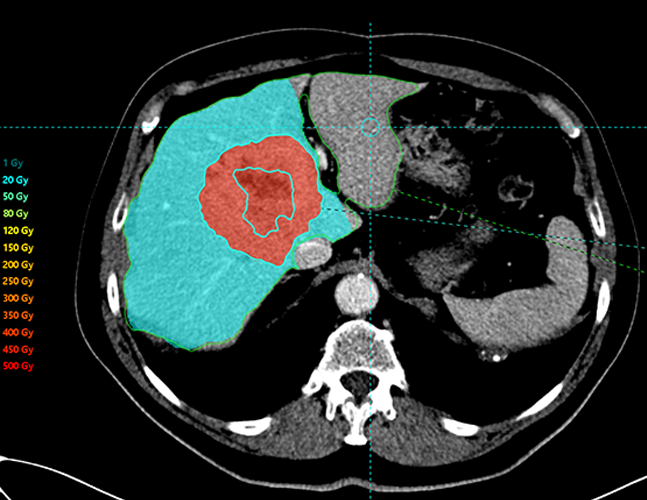

Simplicit90Y™ provides the capability to visualise prospective dose distribution and assess the absorbed dose delivered to the tumour and normal tissue.

By allowing for pre and post-treatment dosimetry, this software can help determine the effectiveness of a

patient’s 90Y SIRT with confidence.

View absorbed dose distribution with isodose

contour line display

Show heterogeneity of absorbed dose distribution in

critical structures, and assess tumour coverage